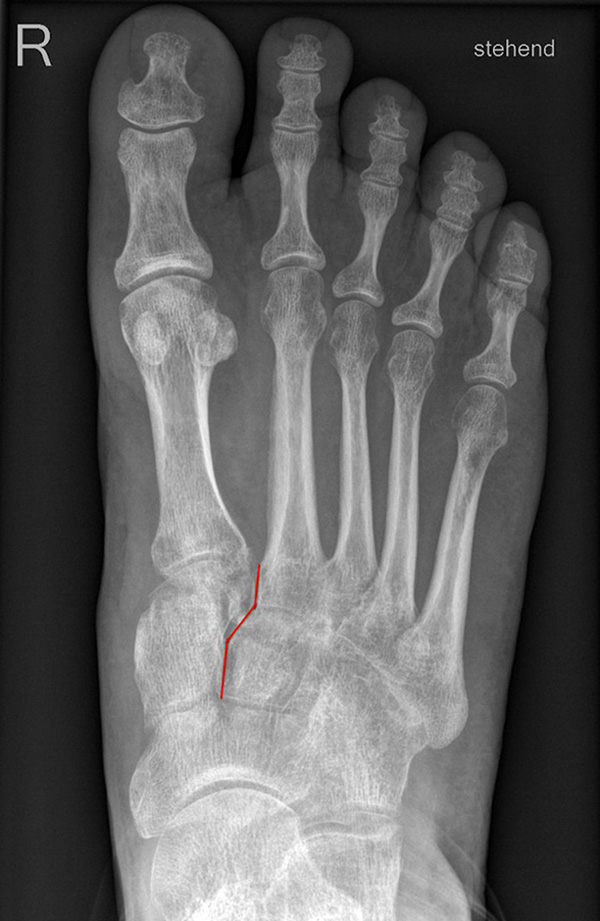

Standardisierte Röntgenaufnahmen des betroffenen Fußes, dorsoplantar (dp), streng seitlich sowie eine Schrägaufnahme werden angefertigt. Diese sollten möglichst unter Belastung angefertigt werden, da in den unbelasteten Aufnahmen insbesondere diskrete Veränderungen häufig nicht sicher zu erkennen sind.

Auf den dp-Aufnahmen sollte der mediale Rand der Metatarsale-2-Basis mit dem medialen Rand des Os cuneiforme intermedium eine homogene Linie ohne Stufenbildung bilden (Abb. 7+8). Außerdem ist auf den Abstand zwischen der Metatarsale-1- und -2-Basis zu achten. Dieser sollte nicht größer als 2 mm bzw. im Vergleich zur Gegenseite nicht mehr als 1 mm erweitert sein. In bis zu 90% der Fälle zeigt sich ein sogenanntes „Fleck sign“ (Abb. 9), ein knöchernes Fragment zwischen der Metararsale-1- und -2-Basis im Sinne eines knöchernen Ausrisses des Lisfranc-Ligaments an der Metatarsale-2-Basis 211936410. Oft liegen zusätzliche Frakturen der Metatarsalebasen oder der Tarsale vor, die ebenfalls identifiziert werden sollten. Bei jeder Mittelfußbasisfraktur sollte umgekehrt an eine Lisfranc-Verletzung gedacht werden.

Zum Lesen der Bildbeschreibung und zur Vollansicht bitte die Bilder anklicken.

In der Schrägaufnahme sollte der mediale Rand des Cuboids mit dem medialen Rand der Metatarsale-4-Basis eine homogene Linie bilden.

In der seitlichen Aufnahme ist auf Dislokationen und Subluxationen in den Tarsometatarsalgelenken sowie auf einen Verlust des Fußlängsgewölbes zu achten. Bei Instabilitäten des 1. Strahls bzw. Abflachung des Fußlängsgewölbes tritt in der Seitaufnahme die plantare Kontur des Os cuneiforme mediale tiefer im Vergleich zur Basis des Metatarsale 5. Darüber hinaus sollte die Cyma-Linie im Bereich des Chopartgelenkes in der Seitaufnahme eine harmonische S-förmige Linie bilden.

Insbesondere bei rein ligamentären, aber auch subtilen Verletzungen können belastete Vergleichsaufnahmen der unverletzten Gegenseite oder Streßaufnahmen des verletzten Fußes unter Bildwandlerkontrolle hilfreich sein 161129584 (Richter 2007).

Aber auch in den belasteten Röntgenaufnahmen sind subtile Frakturen und Luxationen oder rein ligamentäre Verletzungen oft nicht sicher darstellbar 7.